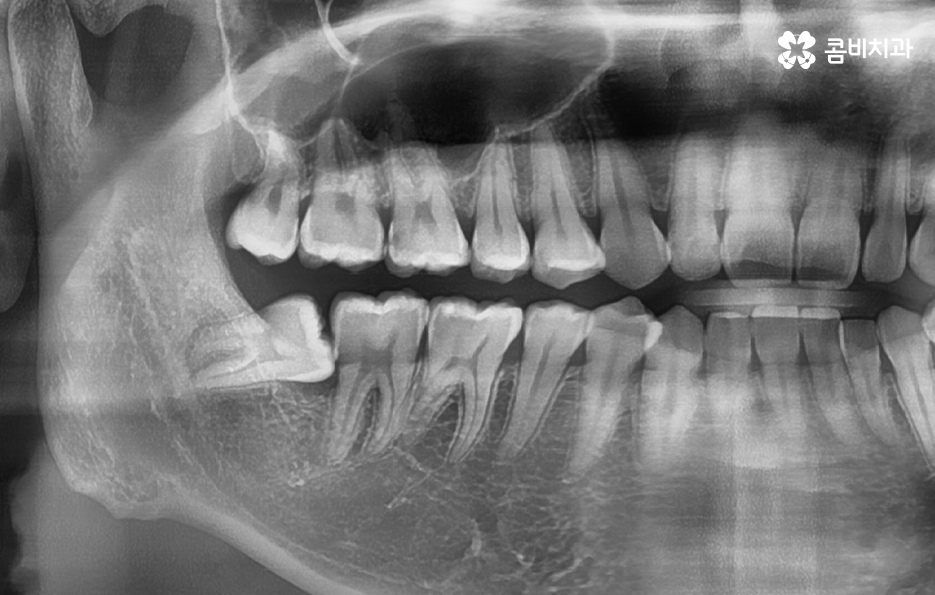

이제 부분매복 사랑니 발치 방법에 대해 좀더 알아보면 사랑니 발치는 단순히 치아를 뽑는 것이 아니라, 잇몸 절개, 치아 분할, 신경 보호 등 여러 과정을 정교하게 고려해야 하기 때문에 첫 번째 단계는 정확한 진단 과정이 우선되어야 할 수 있어요

부분매복 사랑니는 겉으로 보이는 부분만으로는 실제 뿌리 모양이나 뿌리의 깊이를 알 수 없으며 X-ray만으로는 앞 어금니와 얼마나 근접해 있는지, 신경과의 거리, 뼈의 형태를 충분히 판단하기 어렵기 때문에 CT 촬영이 권장되는 경우가 많으며 CT는 3D 분석이 가능하기 때문에 사랑니 발치 시 사고 위험을 줄일 수 있고 절개 방향 등을 정확히 계획하는 데 큰 도움이 되고 있었어요